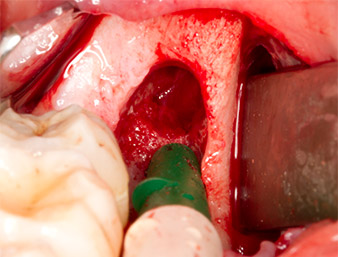

After block and local anaesthesia, the operating site was opened up and the soft tissue exposed for buccal retromolar access (Fig. 3).

The tissue above the root remnant was not completely ossified and consisted for the most part of granulation tissue modified by inflammation (Fig. 4).

To obtain autogenous material for subsequent wound treatment, healthy bone chips were harvested from the surroundings of the root remnant with a piezo surgical instrument (Piezomed B5) (Fig. 5).